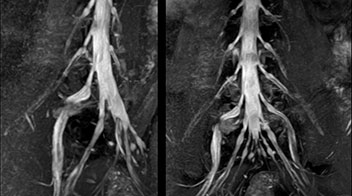

At Northern Fukushima Medical Center in Japan, excellent MRI visualization of nerves helps support confident diagnoses and informs surgical treatment decisions for patients with lower limb symptoms. MRI technologist Tanji and orthopedic surgeon Dr. Yabuki share how direct nerve visualization with the 3D NerveVIEW method adds information when diagnosing atypical herniations. The additional insights changed their way of working and benefit their patient care, as illustrated by some clinical examples.

“In patients with lower extremity neurological symptoms, NerveVIEW helps us to determine the disease matching the patient’s symptoms by directly visualizing the nerves. We use the sequence mainly, when there is suspicion of intraforaminal stenosis, extraforaminal stenosis or lateral disc herniation, which is often based on routine T2- and T1-weighted images. Additionally, the excellent depiction of the course of nerves makes NerveVIEW a good navigator when applying treatment such as block therapy or surgery.”

“In such case, we would then browse through axial T2-weighted MR images slice by slice and mentally reconstruct the actual situation based on both radiculography and MRI. Fortunately, NerveVIEW can now very well show nerve courses and presence of nerve compression or edema in one single image series.” “We have often seen NerveVIEW directly depict details of the nerve compression that were not observed by radiculography. Therefore, we think that with NerveVIEW we can reduce the number of invasive examinations, especially for some patients with lumbar plexus symptoms.”

“The intra-luminal signal of veins, especially around the intervertebral space, can be suppressed well with NerveVIEW. As a result, we can easily observe the detailed nerve structure around the posterior ganglion,” he says. “This is why we use 3D NerveVIEW for intraforaminal stenosis and extraforaminal stenosis/herniation (lateral disc herniation). On the other hand, if herniation is suspected to exist inside the dorsal root ganglion (DRG), balanced TFE or ProSet-FFE is applied. NerveVIEW is not suitable for evaluating the median type of herniation.” The SE-EPI DWI-based method for MR neurography works well for large FOV exams like whole-body MRI, but focal examination of nerves is often limited by the attainable spatial resolution (both inplane and slice direction) and geometric distortion. “3D NerveVIEW achieves higher in-plane resolution – close to our other routine spine sequences – and the source images can be used instead of adding a fat-suppressed T2-weighted sequence,” Tanji says.

According to Tanji, methods such as ProSet FFE, STIR or 3D VISTA are anatomically nonselective because background signals, for instance from blood vessels, often interfere with nerves, which hampers evaluation of details, especially at the peripheral side of the nerves.